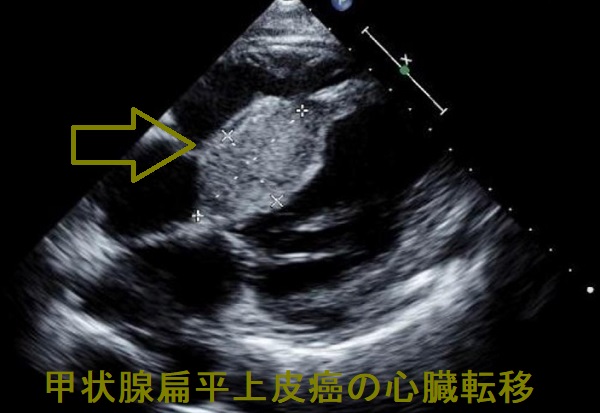

甲状腺癌による転移性心臓腫瘍は、甲状腺未分化癌が最も多く、次いで甲状腺濾胞癌です。

転移部位は右心室が多く、左心室転移は少ない。リンパ行性転移、血行性転移いずれも大静脈から右心室内に至る経路が考えられます。左心系に転移する場合、

- 肺転移巣から肺静脈

- 右心室から肺動脈→肺静脈

を通り、左心系の心内膜に接着・増殖する可能性が考えられます。 (Jpn. J. Clin. Oncol 18:195-201, 1998)